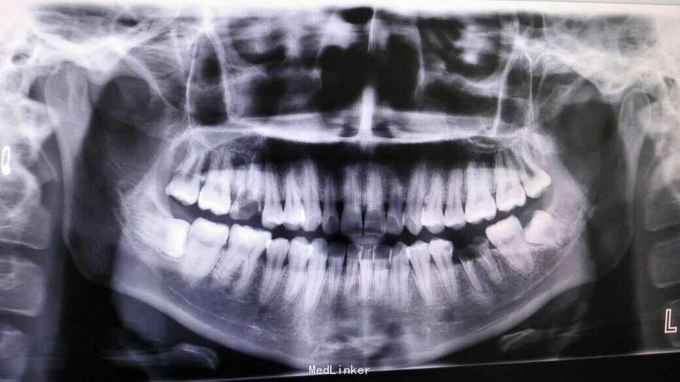

水平阻生智齿拔除

患者,男,35岁,智齿阻生拔除

一例水平阻生智齿拔除术